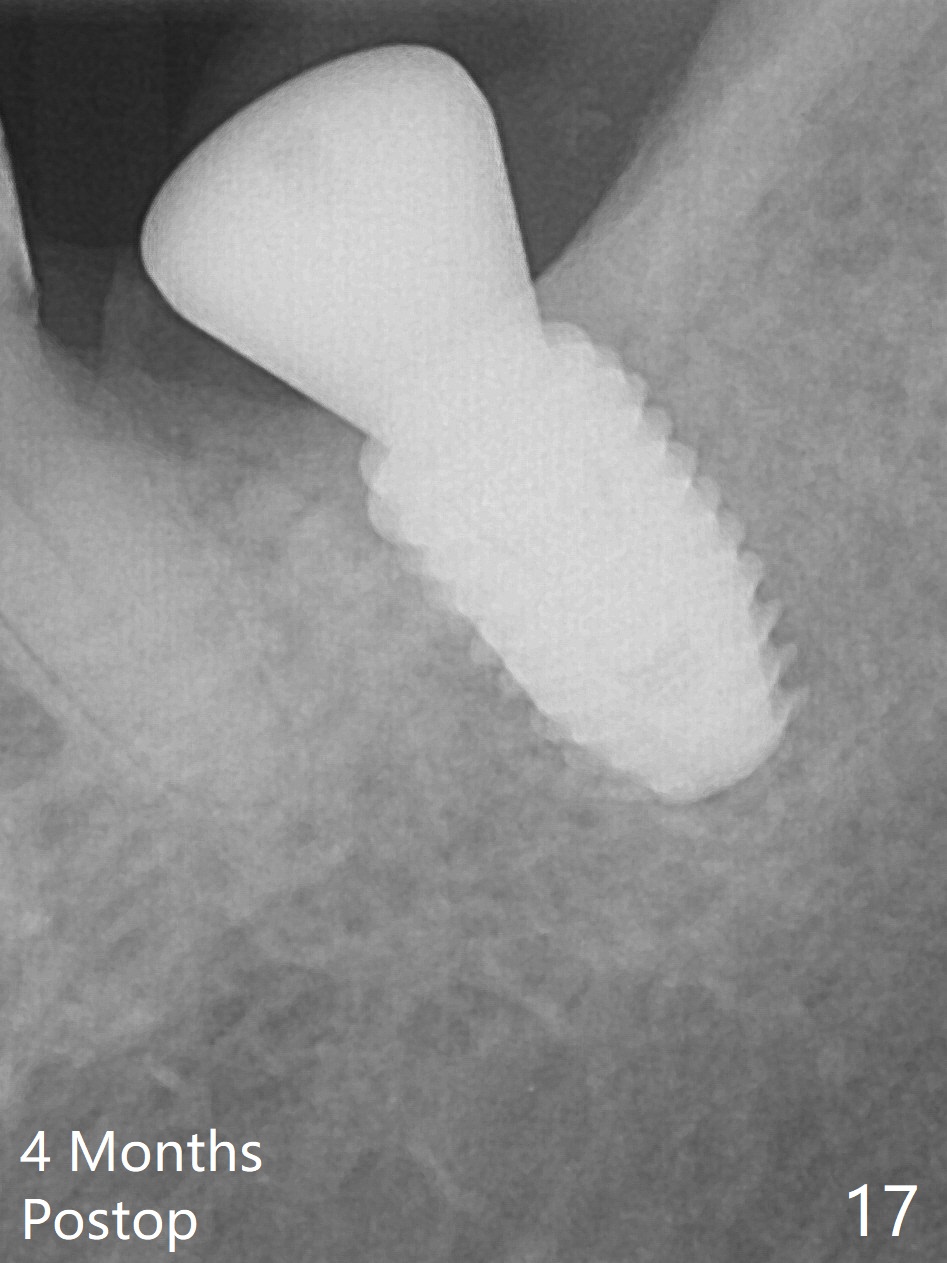

There is no apparent bone loss 4 months postop (Fig.10).  There is chewing pain in spite of occlusal adjustment 7 months post cementation (Fig.11-13: increased radiolucency around the implant).  The crown/abutment is removed and a healing abutment is placed (6x3 mm); the implant is stable.  The patient return for re-evaluation in 3 months (15 months postop); radiolucency appears to reduce (Fig.14).  But there is pain when the healing abutment is being removed.  After local anesthesia, the implant is removed with a wrench.  Following debridement of the osteototomy (intact, although tender), a 5x10 mm dummy implant with SLA surface is placed (Fig.15).  After 5.5 mm tap, a 5.5x8.5 mm implant is placed with >50 Ncm (Fig.16).  A 6.8x5 mm healing abutment is placed, followed by periodontal dressing.  Re-analysis of preop CBCT shows that the bone density at the site is low: 70 units average.  Progressive loading is necessary for this case 4-6 months postop.  The soft and hard tissues around the implant seem to heal 4 months postop (Fig.17).